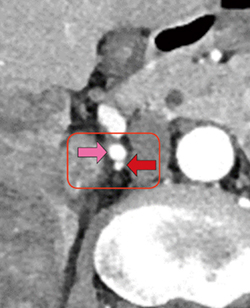

今回の症例では,上行する栄養血管が完全に右腎動脈に重なり,その上下の距離も1mm程度と非常に近いために(図8,9),アンギオ撮影中に角度をつけて再度撮影したとしても,発見は困難であったと考える。

図8 造影CT早期相 |

図9 造影CT早期相(図8の拡大像) |